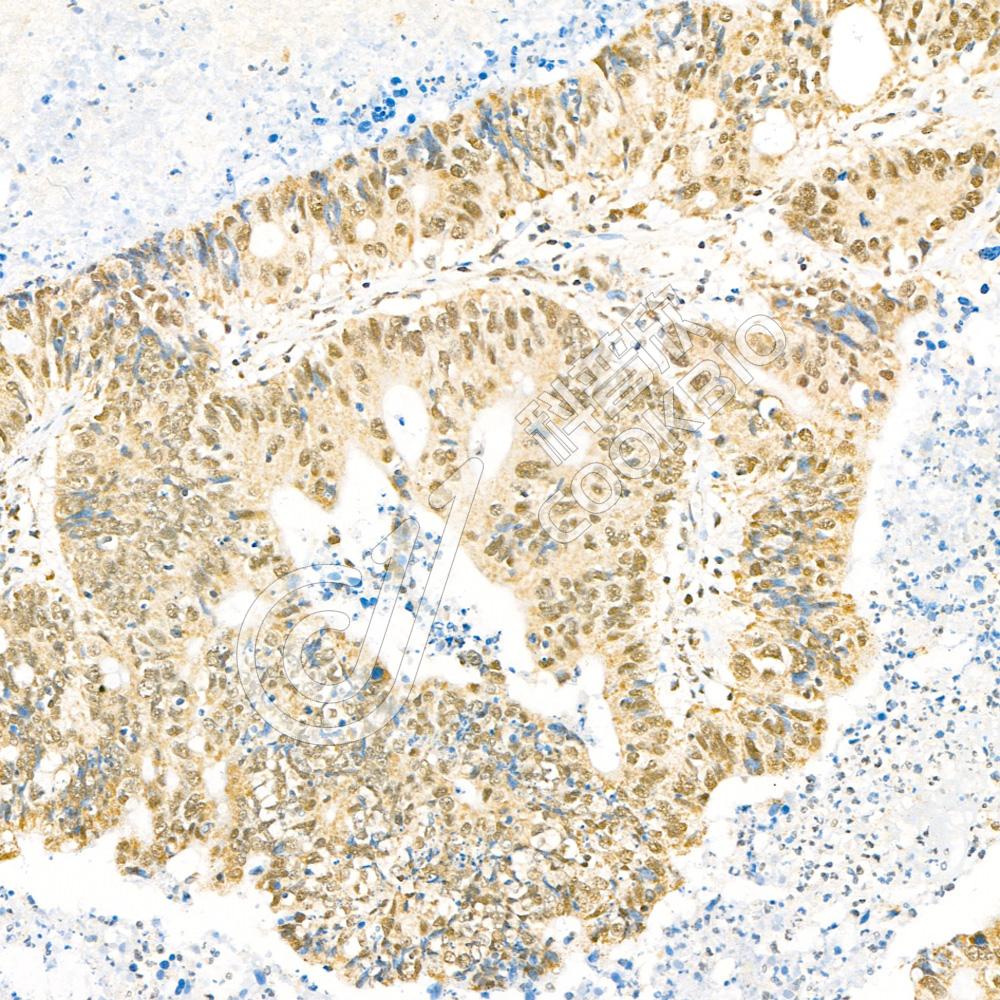

图像

WB检测NKIAMRE蛋白(货号 K1337959).